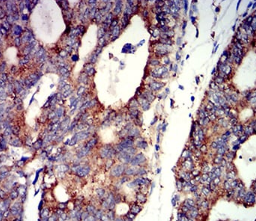

IHC    1/100 - 1/500